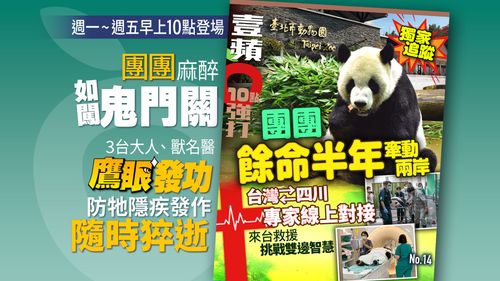

...對生命安全最具威脅疾病包括:中暑、腸梗阻、腸鈕轉、腸套疊、急性胰腺炎、腎功能衰竭等。 這次團團出現...